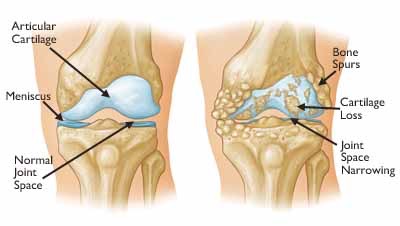

The normal knee joint

Smooth Cartilage seen in the normal non-arthritis knee joint.

The Normal Knee

The knee is a critical joint. Unfortunately it is also commonly injured and develops arthritis in many people.

The normal knee consist of smooth articular cartilage which is strong and resilient. It allows the knee to move smoothly and without pain.

The meniscus provides cushioning and some stability to the knee.

The Arthritic Knee

Arthritis causes a wearing out of the knee cartilage

Knee arthritis is a progressive wearing out of the normal articular cartliage that lines the moving surfaces of the knee. As the cartilage wears away it can become frayed and rough, and the thickness of the protective cartilage decreases. This wear and tear can be a slow and progressive process or can develop because of a prior injury. As the arthritic process progresses it can result in bone rubbing on bone, and become progressively more painful. The “environment” in an arthritic knee allows the “breaking down” (catabolic effect) process of the cartilage and meniscus to continue. The wear and tear cycle just continues until the knee is completely worn out.